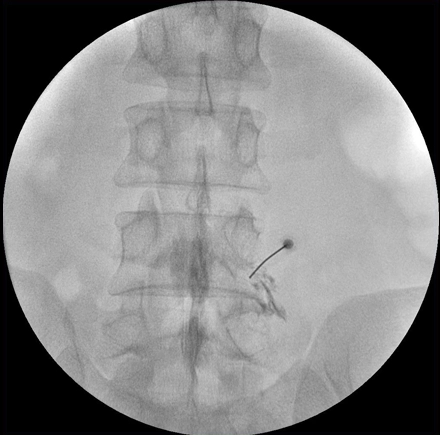

Цифровые изображения с матрицей 1024x1024 помогут увидеть мелкие детали

Визуализируйте мелкие детали сложных структур, просто наведите аппарат и нажмите кнопку экспозиции, и цифровая цепи формирования изображений с матрицей 1024x1024 сделает всю сложную работу. Эта цифровая цепь включает в себя усовершенствованные средства шумоподавления и подчеркивания контуров в двумерных изображениях. Благодаря высококачественным изображениям можно быстро визуализировать сложные костные структуры для более точной установки имплантатов.